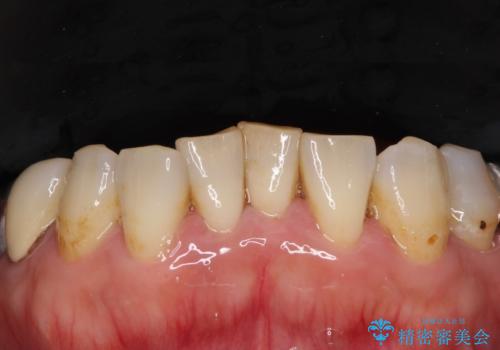

- 歯茎からの出血、入れ歯、歯の欠損、デコボコの前歯などを気にして来院された患者様です。

大の歯科治療嫌いとのことでしたが、今回の治療を契機にしっかりと治療を行いたいとのことでした。

油断をするとすぐに汚れが溜まって歯肉が腫れてきてしまうため、今後も定期的なメインテナンスが重要となります。